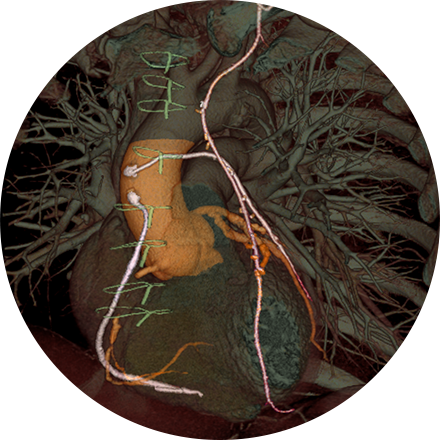

Angiogram

An angiogram is an X-ray exam of the arteries and veins to diagnose blockages and other blood vessel problems. It can reveal the integrity of the cardiovascular system in specific areas throughout the body. Combined with the use of intravenous contrast medium injected via a catheter, an angiogram identifies areas of blockage or damaged vessels within the circulatory system. CT and MRI may also be used to gain additional images of the arteries.